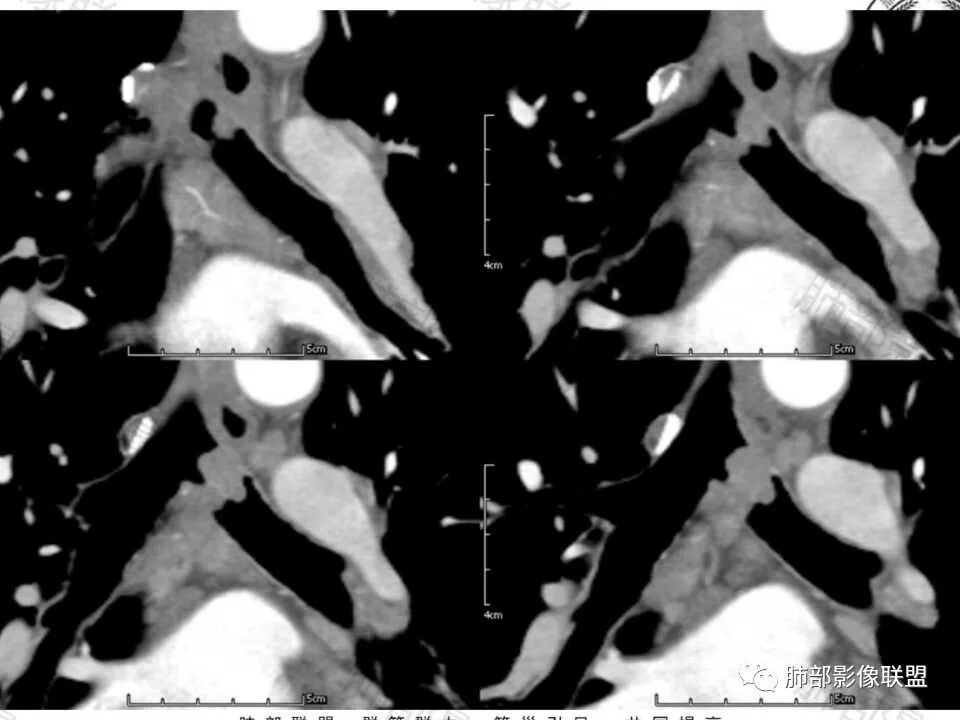

1、病灶腔内为主

2、局部软骨不连续,壁外有增厚,提示局部软骨破坏,壁外有病灶

3、明显强化

定位:左主支气管

定性:考虑低度恶性肿瘤性病变